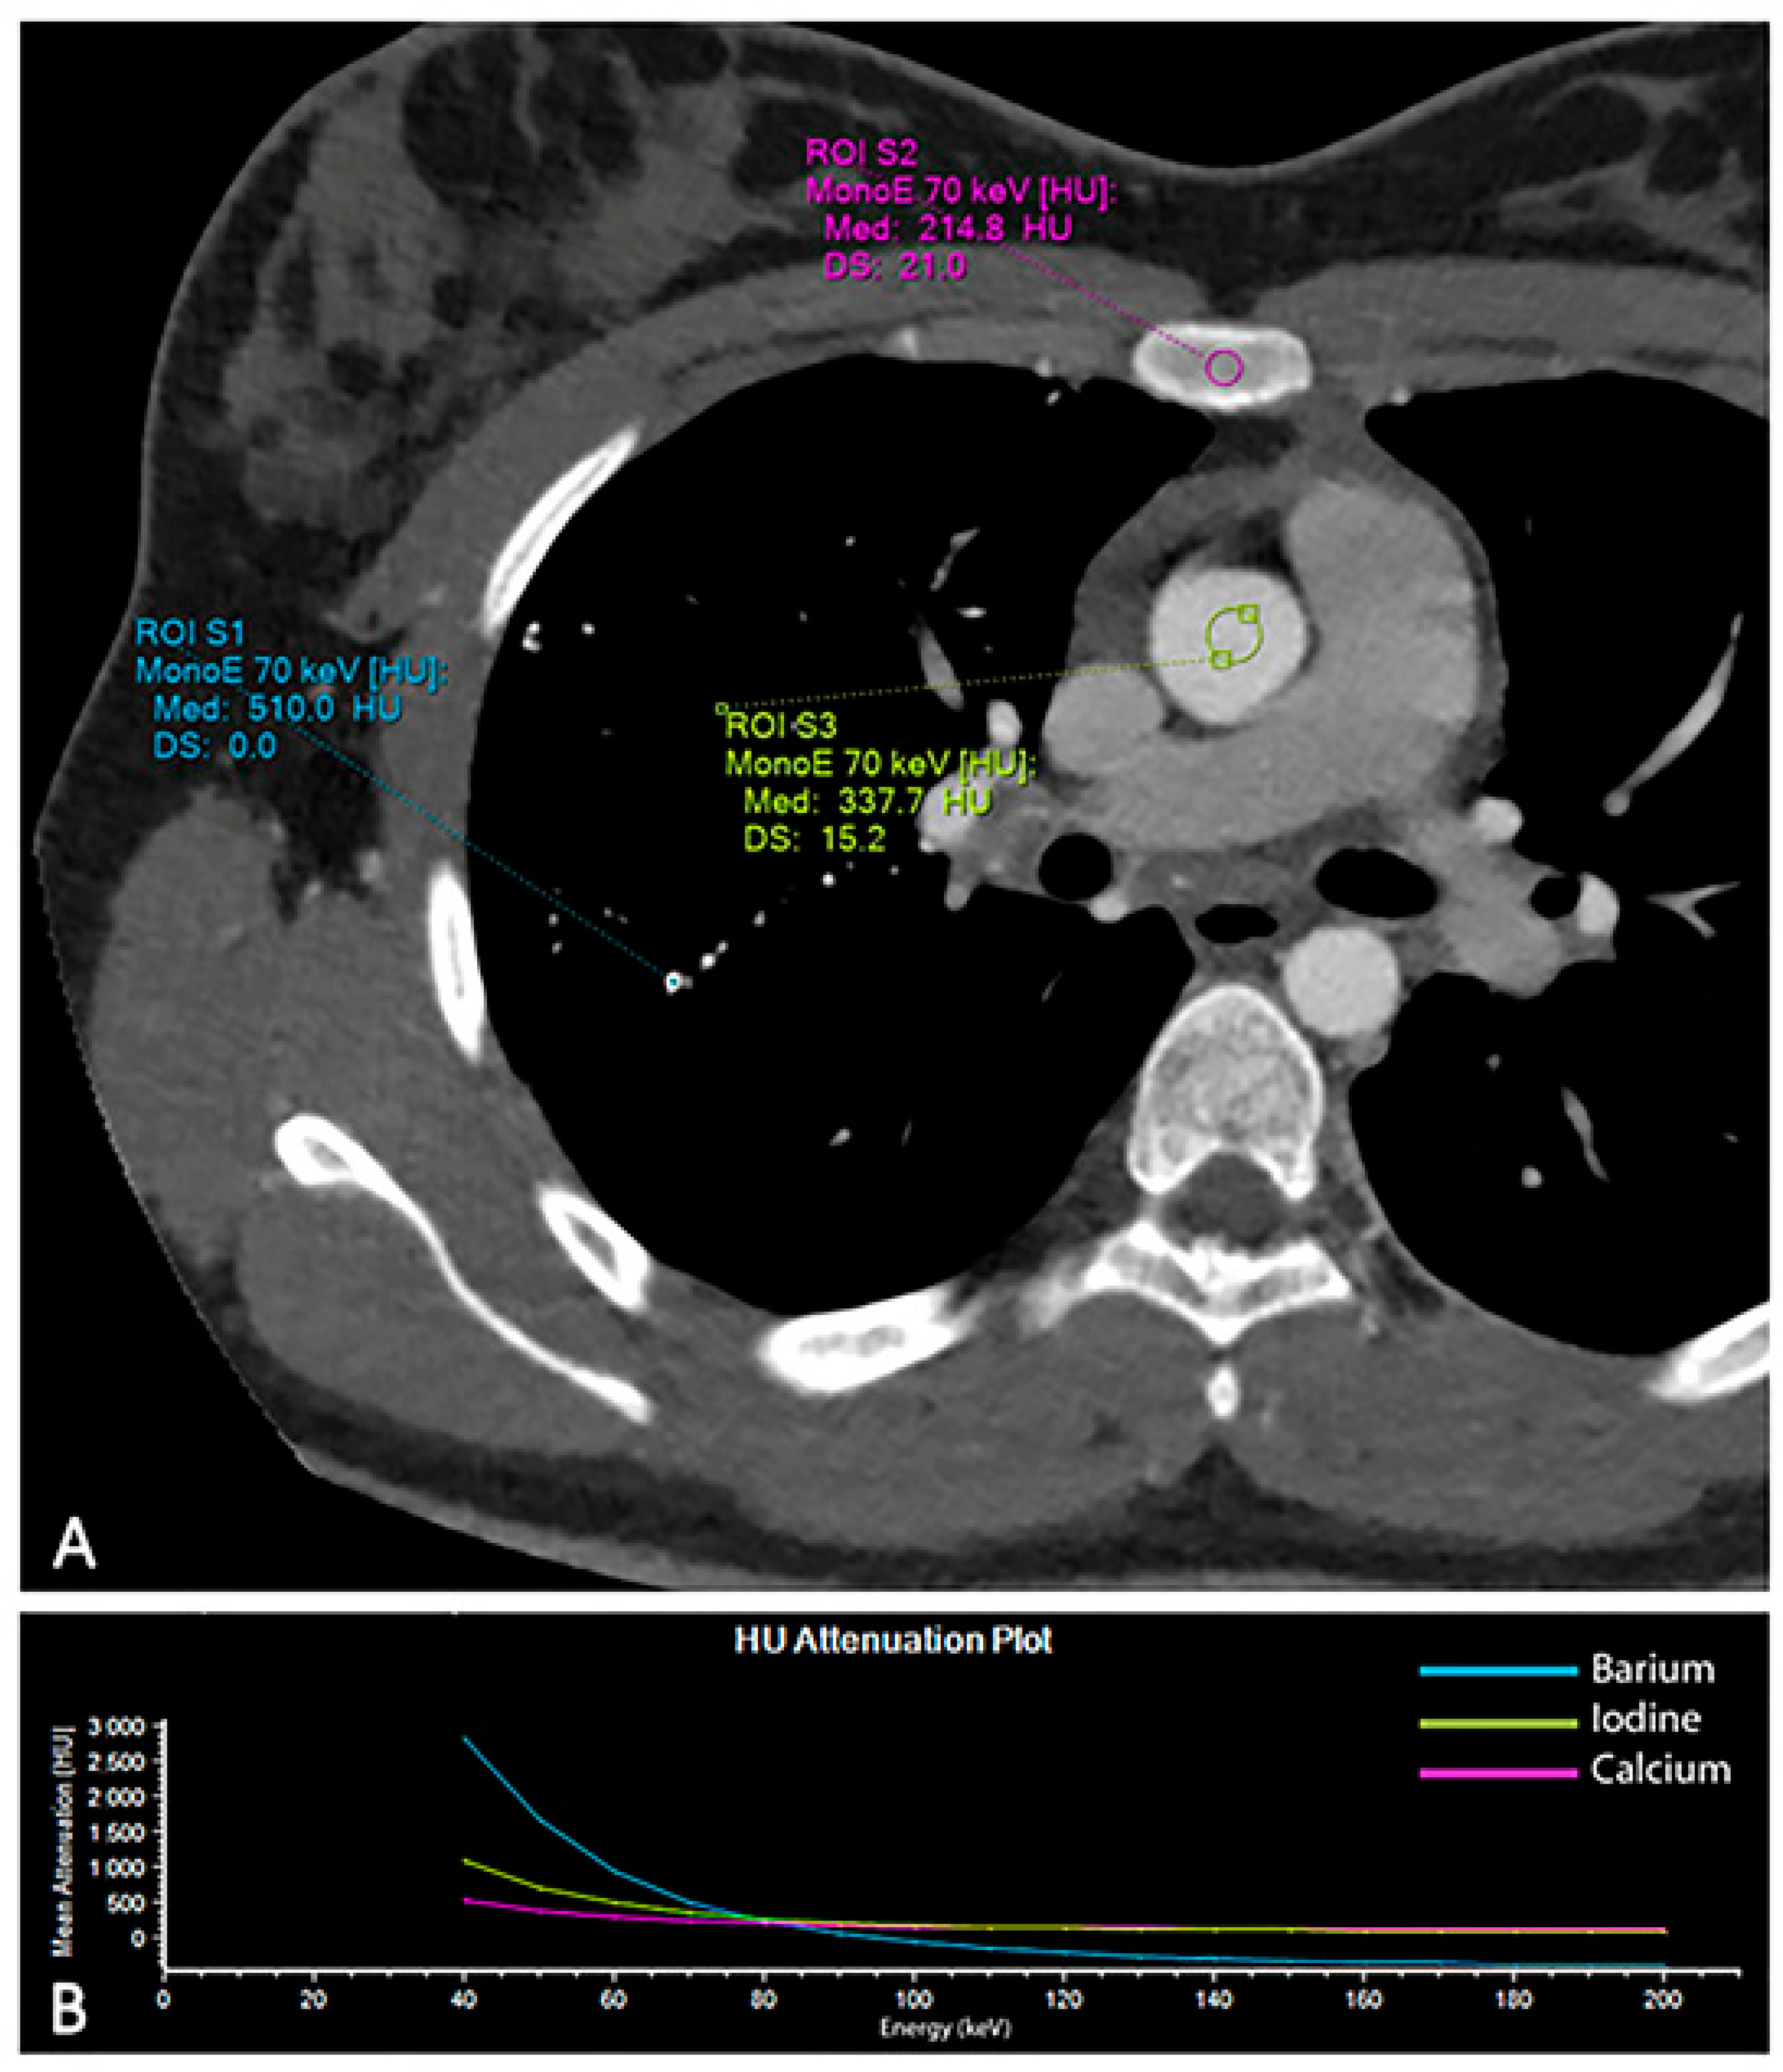

A comprehensive spectral evaluation was performed to characterize the high-density nodules. Firstly, virtual non-contrast reconstruction was obtained to derive the pre-contrast images (Figure 2A,B). All the lesions were removed along with the iodinated contrast medium, suggesting high Z number of the material and excluding the presence of calcium-containing lesions (Z = 20). Regions of interest were placed within the micronodules, in the sternum and in the aorta to investigate differences in attenuation (Figure 3). Despite the curves showing similar patterns, increasing at low energy levels (i.e., 40 keV), the lung nodules had the highest profile, even when compared to the iodine attenuation curve. Color-coded reconstruction maps based on Z-effective number also revealed that the lung nodules were composed of a material with higher Z number than iodine (Figure 2C,D). A careful review of the patient’s medical record showed that the patient had undergone a barium-swallowing study in another institution two years earlier. This study was interrupted due to the transit of a considerable amount of contrast material into the right bronchial tree through a small tracheoesophageal fistula (Figure 4). Patient’s medical history, together with spectral information, allowed for diagnosis of barium lung granulomas related to a previous swallowing study.

Figure 3.

Analysis of the attenuation curves of different materials based on spectral CT data. Regions of interest were placed within the aorta (iodine), in the pulmonary micronodules (barium) and in the sternum (calcium) to investigate the attenuation curves of the different materials (A). The graph displays how each material has exclusive changes in attenuation at the different energy levels (B).